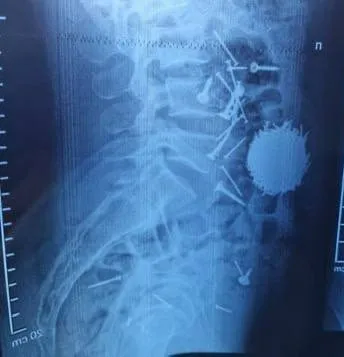

В Узбекистане мужчина из-за стресса и кредитов проглотил около 100 гвоздей и саморезов, сообщает Zakon.kz.

В Самарканде 29-летнему мужчине экстренно провели операцию, передает Telegram-канал "Oblakouz". Ее сделали после того, как врачи обнаружили в желудке мужчины почти 100 гвоздей и саморезов общим весом 200 гр.

По данным медиков, мужчина находился в состоянии сильного стресса и не контролировал свои действия.

"Операция прошла успешно, сейчас его состояние стабильное", – говорится в публикации.